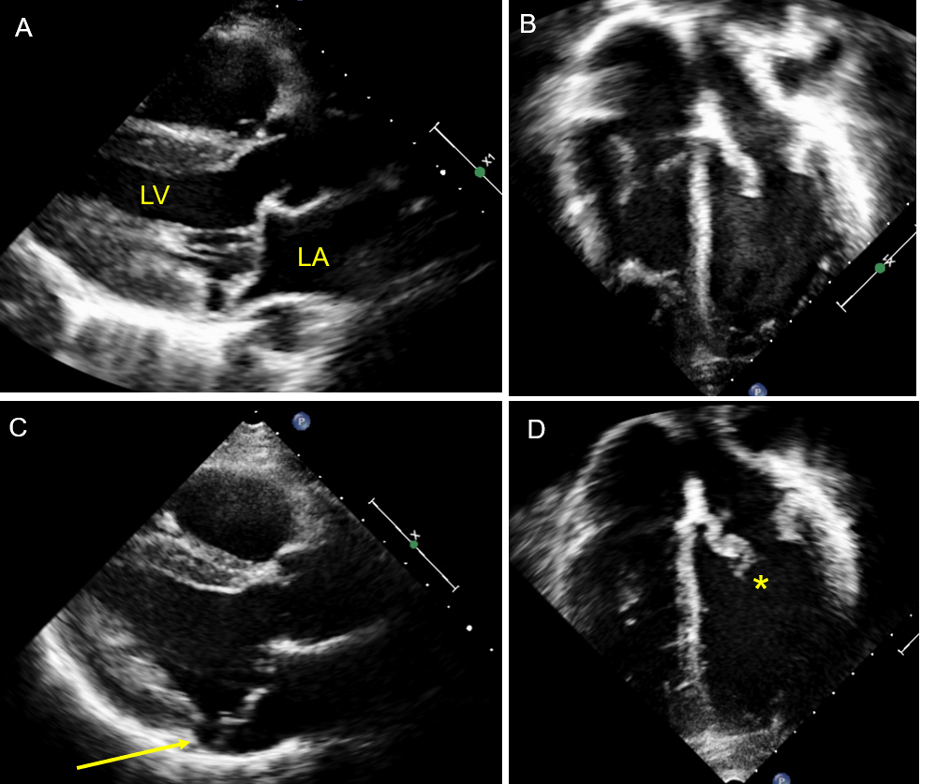

We report a 20-year-old nonsyndromic female with a history of PVD identified at age 6 following evaluation for palpitations. Early echocardiography revealed mitral valve prolapse (MVP) without regurgitation and tricuspid valve prolapse with mild regurgitation. By age 13, echocardiography demonstrated redundant dysplastic atrioventricular valves with mild regurgitation across all valves. Physical exam revealed hypermobility (Beighton score 9) without other cutaneous or skeletal features of a connective tissue disorder. Genetic testing was negative for FLNA variants.

A three-generation family history revealed MVP and progressive valvular disease in the patient’s mother and maternal aunt. The aunt, who experienced heart failure and required implantable cardioverter-defibrillator (ICD) placement and ablation for ventricular arrhythmias, was found to carry a heterozygous nonsense variant in TAB2 (c.430C>T; Q135X). This variant is absent in large population databases and is classified as likely pathogenic. Cascade testing identified the variant in the proband and mother, confirming segregation with disease. The maternal grandmother lacked the variant and was asymptomatic.